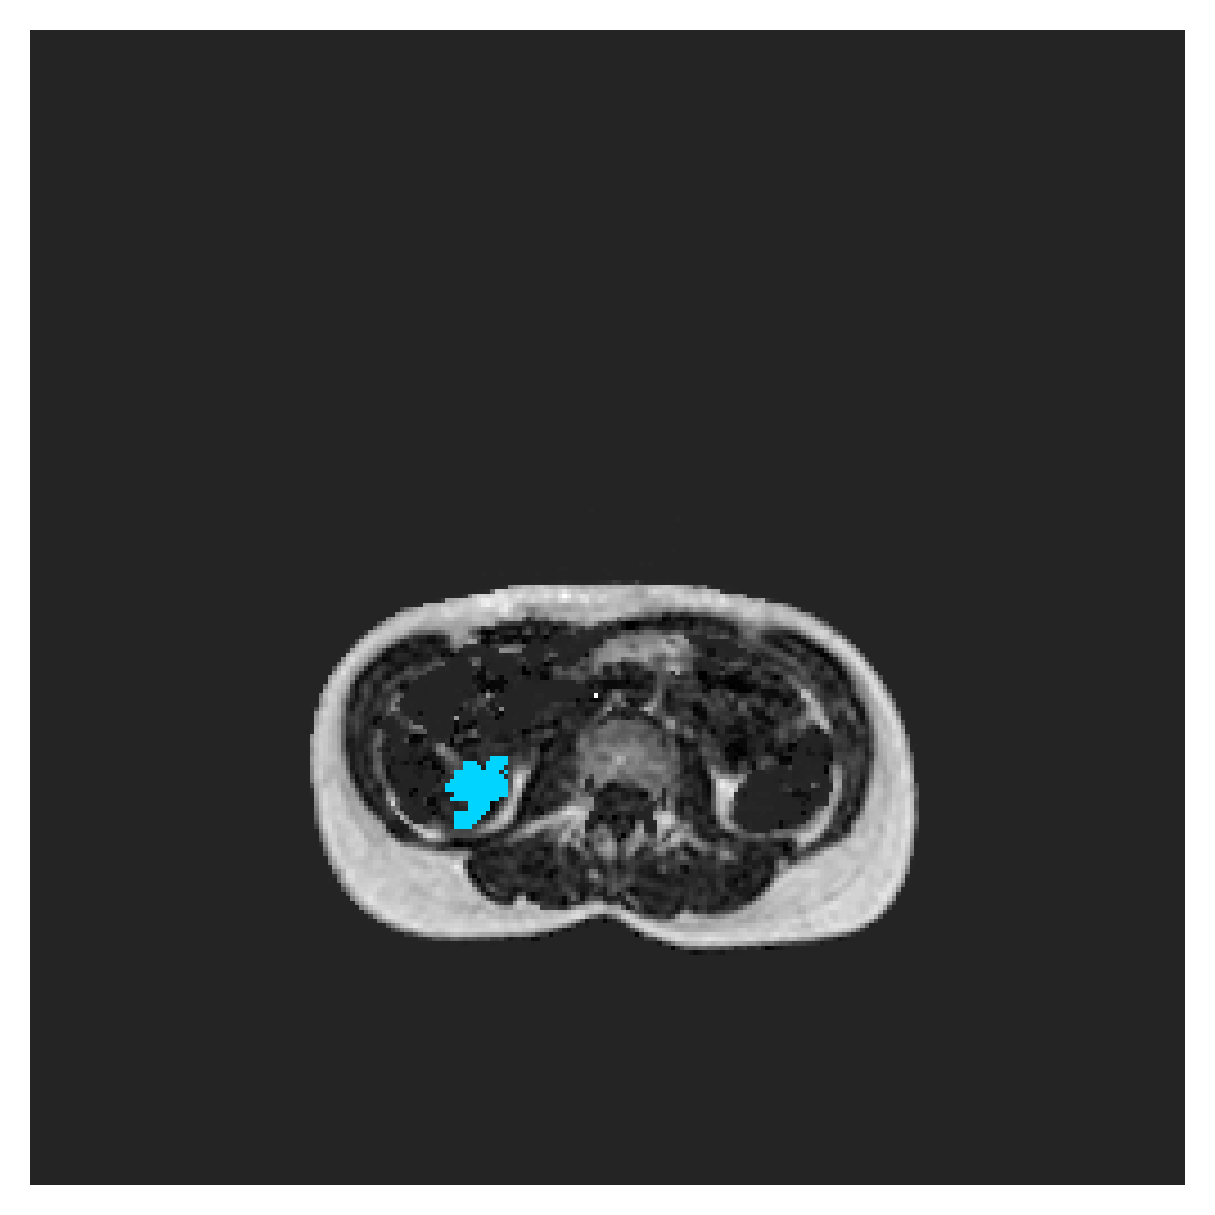

The images contain two channels, one for water and one for fat content. For training, we normalize the volumes (per channel) and use 2D slices in the coronal plane, sized . The weak annotations are created synthetically, following the same procedure as described for the ACDC dataset.